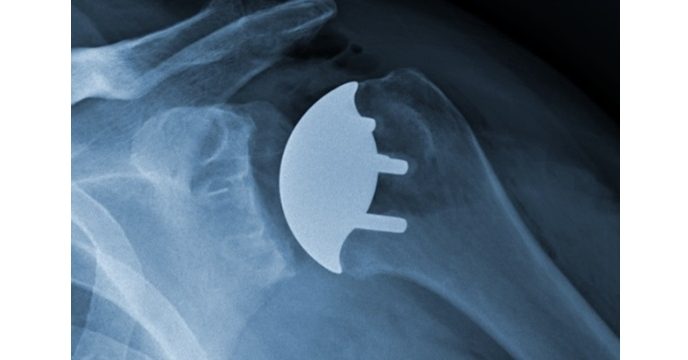

Recon Top Stories Catalyst OrthoScience Announces 5-8 Year Data Reporting Significant Functional Improvement and Pain Reduction for Anatomic Total Shoulder Arthroplasty byTim AllenJune 4, 2025